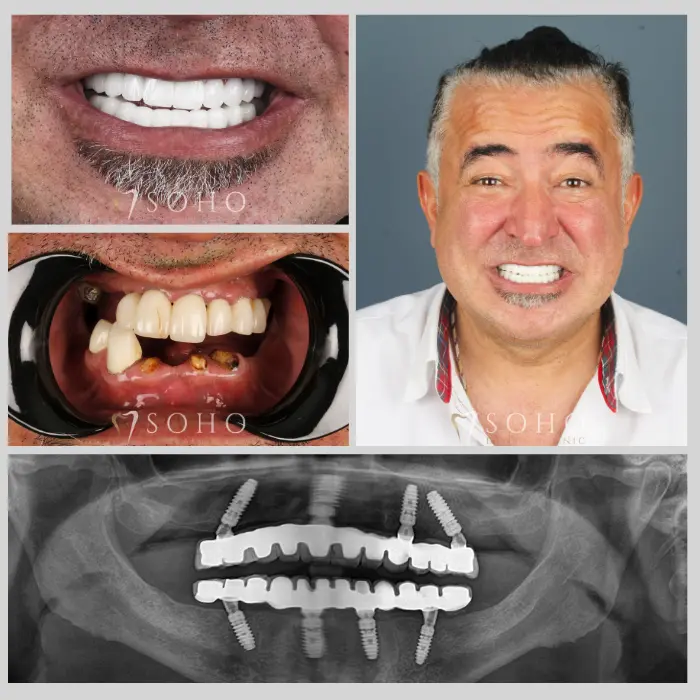

Real Patients. Real Smiles.

Explore the journey of our international patients through authentic visuals, elegant transformations, and moments captured inside Soho Dental Clinic. Let their stories inspire your own.

From First Visit to Final Smile.

Explore real patient stories captured in every transformation. These are more than smiles — they are renewed confidence, achieved with care and precision at Soho Dental Clinic.